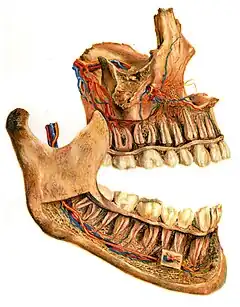

In jawed vertebrates, the mandible (from the Latin mandibula, 'for chewing'), lower jaw, or jawbone is a bone that makes up the lower – and typically more mobile – component of the mouth (the upper jaw being known as the maxilla).

The jawbone is the skull's only movable, posable bone, sharing joints with the cranium's temporal bones. The mandible hosts the lower teeth (their depth delineated by the alveolar process). Many muscles attach to the bone, which also hosts nerves (some connecting to the teeth) and blood vessels. The jawbone is particularly essential for chewing food.

The body of the mandible is curved, and the front part gives structure to the chin. It has two surfaces and two borders. From the outside, the mandible is marked in the midline by a faint ridge, indicating the mandibular symphysis, the line of junction of the two halves of the mandible.[6] This ridge divides below and encloses a triangular eminence, the mental protuberance (the chin), the base of which is depressed in the center but raised on both sides to form the mental tubercle. Just above this, on both sides, the mentalis muscles attach to a depression called the incisive foramen.[6] Vertically midway on either side of the body, below the second premolar tooth, is the mental foramen, through which the mental nerve and blood vessels pass.[6] Running backward and upward from each mental tubercle is a faint ridge, the oblique line, which is continuous with the anterior border of the ramus.[6] Attached to this is the masseter muscle (related to mastication), the depressor labii inferioris and depressor anguli oris (which support the mouth), and the platysma (extending down over much of the neck).[6]

From the inside, the mandible appears concave. On either side of the lower symphysis is the mental spine (which can be faint or fused into one), to which the genioglossus (the inferior muscle of the tongue) attaches; the geniohyoid muscle attaches to the lower mental spine. Above the mental spine, a median foramen and furrow can line the symphysis. Below the mental spine is an oval depression where the digastric muscle attaches. Extending backward and upward on either side from the lower symphysis is a ridge called the mylohyoid line, where the mylohyoid muscle attaches; a small part of the superior pharyngeal constrictor muscle attaches to the posterior ridge, near the alveolar margin. Above the anterior ridge, the sublingual gland rests against a smooth triangular area, and below the posterior ridge, the submandibular gland rests in an oval depression.